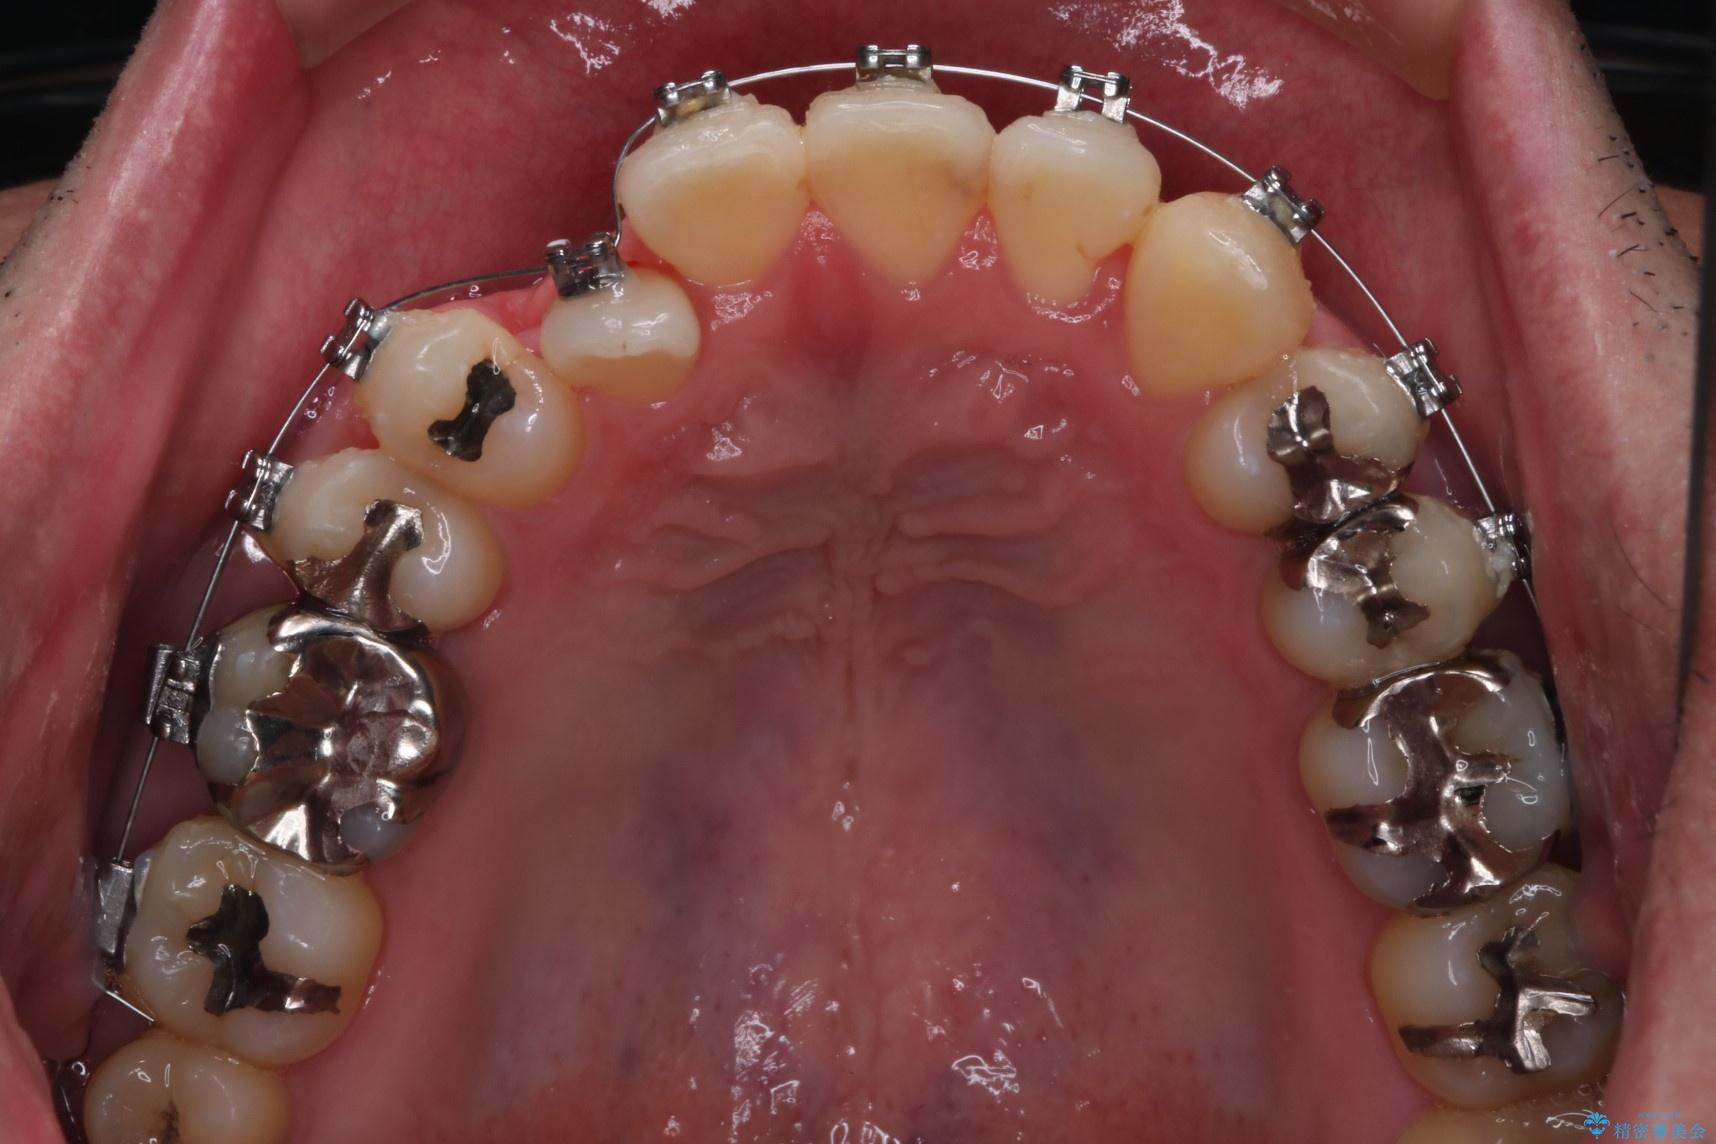

- 矯正装置

- メタル装置

- 右上2番目の歯が舌側転位していることと前歯の叢生(がたつき)を主訴に来院されました。

右上の犬歯が初診時よりかなり歯根露出しており、矯正の力をかけるとさらに歯根露出するリスクがあるため、右上の2番目の歯を前に出すためにも

右上の犬歯を抜歯して歯並びを整える治療計画を立てました。

下のがたつきをとるために、IPR(歯と歯の間を削る処置)も行って歯を並べていきます。